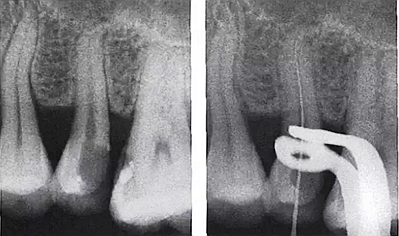

3.根管內(nèi)出現(xiàn)明顯的側(cè)支根管時(shí)。

解決:會(huì)通過側(cè)枝根管形成短路,當(dāng)銼針到達(dá)側(cè)枝根管口試即提示到達(dá)或超出根尖。

需結(jié)合X光片共同確認(rèn)!

5.用X線片輔助確認(rèn)

1.進(jìn)入側(cè)枝根管